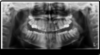

Sur une radio panoramique on la localise : couchée, plus ou moins haute, au palais ou côté joue … tout est possible ! Ce que nous pouvons remarquer sur les radios de notre patient.

4e radio : Canine arrivée à destination